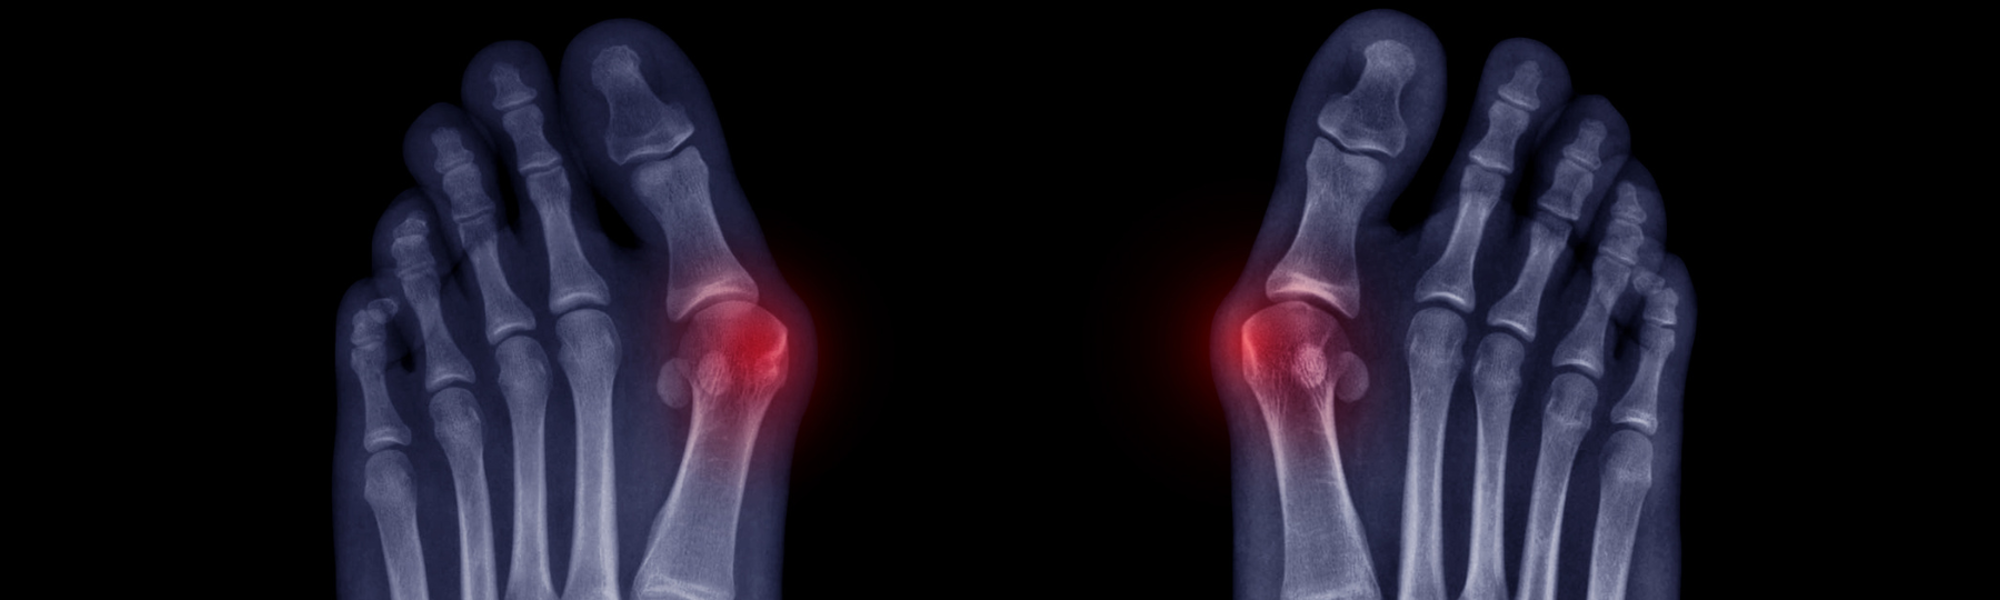

A bunion is more than just an overgrowth of the bone. It's a complex, three-dimensional deformity caused by an unstable joint in the middle of the foot. This instability allows the long bones located in the mid-foot to lean out of alignment, resulting in a bump on the base of the big toe that can be painful and make it difficult to wear certain types of shoes. They can be classified as mild, moderate or extreme and are progressive, meaning they do not resolve on their own without the help of surgery.

Statistics show that almost 25% of U.S. adults suffer from bunions. 87% of these cases involve the metatarsal bone having an irregular rotation. Unfortunately, most traditional bunion surgeries are two-dimensional, focusing only on the visible bump and failing to address the root cause—an unstable joint. When the problem isn't treated correctly, there is a 12x chance the bunion will return.